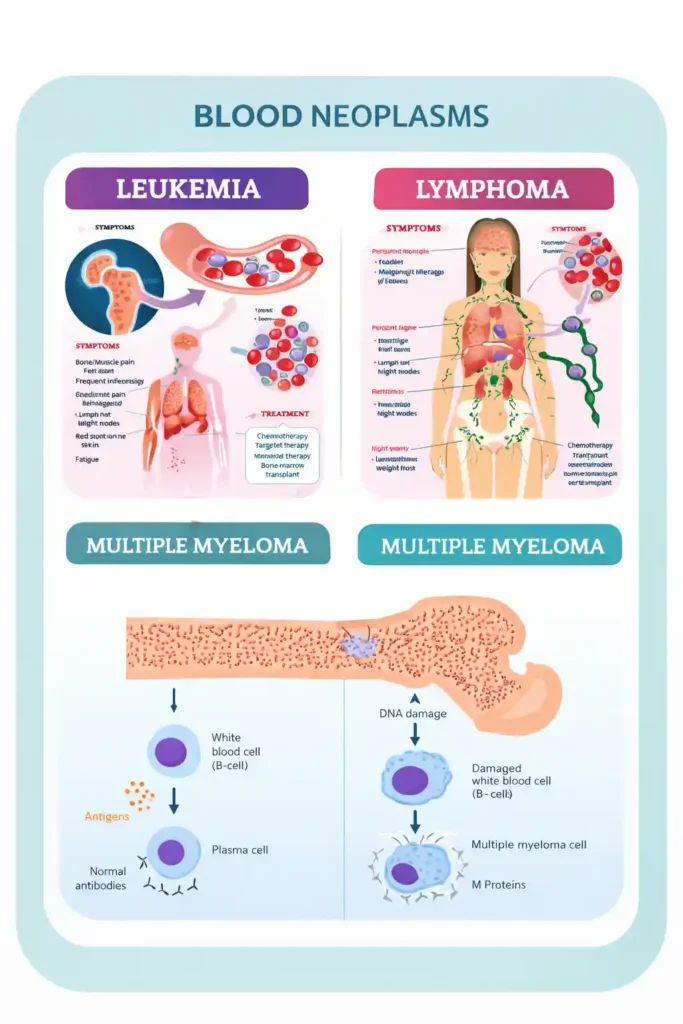

In blood cancers, stem cell transplantation plays a direct therapeutic role.

The Three main types of:- Leukemia – Cancer of white blood cells

- Lymphoma – Cancer of the lymphatic system

- Multiple Myeloma – Cancer of plasma cells in bone marrow

Role:

- Replaces damaged bone marrow after high-dose chemotherapy

- Restores red blood cells, white blood cells, and platelets

- Rebuilds immune system

- Reduces risk of relapse in selected cases

Definition:

Blood cancer refers to cancers that affect the blood, bone marrow, or lymphatic system. These cancers interfere with the body’s ability to produce healthy blood cells.

Common Symptoms:

- Persistent fatigue

- Frequent infections

- Easy bruising or bleeding

- Bone pain

- Swollen lymph nodes

- Unexplained weight loss

- Night sweats